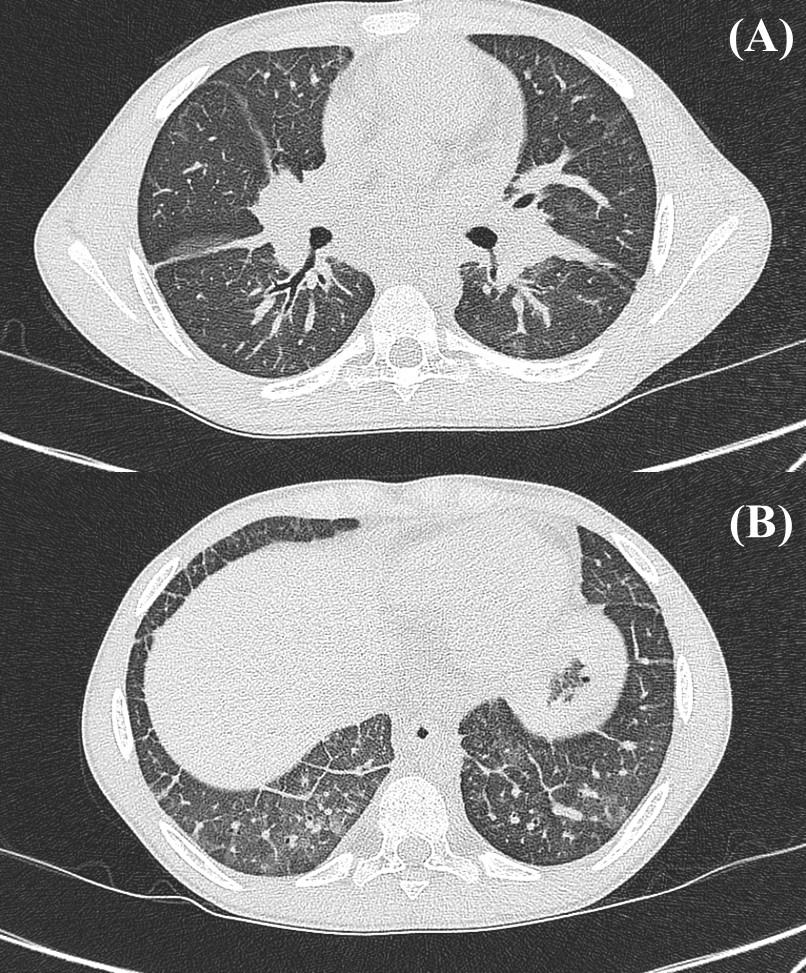

Case 1 Chest Computed Tomography Scan Prior to Rituximab-Cyclophosphamide Induction

sJIA-LD characterized by the following: (A) Interlobular septal and peribronchial thickening. (B) Bronchiectasis and peribronchial thickening in the bilateral lower lobes. *sJIA-LD, systemic juvenile idiopathic arthritis-associated lung disease.